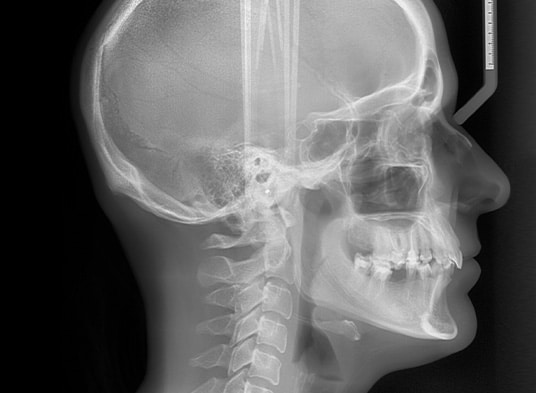

Zdjęcia cefalometryczne

Zdjęcia cefalometryczne są kluczowe przy leczeniu ortodontycznym, umożliwiając dokładną analizę ułożenia zębów w kości. Co więcej tego typu zdjęcie pomaga ortodoncie ocenić wzajemną relację szczęki oraz żuchwy.